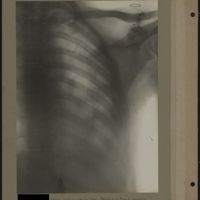

0031 - Page 27 - [Radiographie du thorax]0031 - Page 27 - [Radiographie du thorax]

0042 - Page 38 - [Radiographies du thorax]0042 - Page 38 - [Radiographies du thorax]

0058 - Page 54 - [Radiographie du thorax]0058 - Page 54 - [Radiographie du thorax]

0073 - Page 69 - [Radiographie du thorax]0073 - Page 69 - [Radiographie du thorax]

0082 - Page 78 - [Radiographie du thorax]0082 - Page 78 - [Radiographie du thorax]